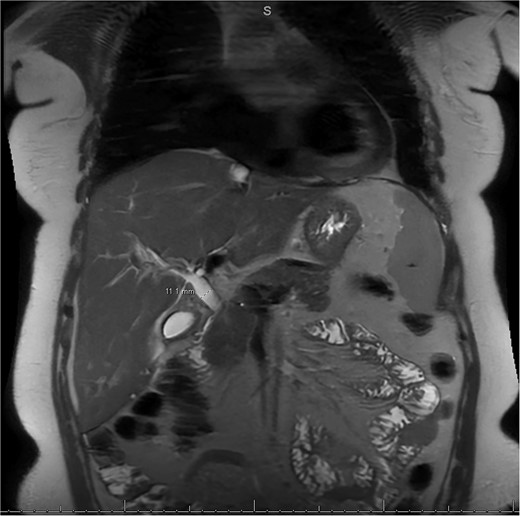

MRI/MRCP from second hospitalization demonstrating recurrent cholelithiasis.

A 49-year-old female with a history of ADPKD and multiple liver cysts, 13-months status post subtotal cholecystectomy, endoscopic retrograde cholangiopancreatography with biliary sphincterotomy and balloon stone extraction, presented to the emergency department with fever and a 4-day history of discomfort in the right upper quadrant. At the time of the initial cholecystectomy, total cholecystectomy could not be performed due to extensive adhesions, and subtotal cholecystectomy with complete evacuation of the stones was done instead. Magnetic resonance cholangiopancreatography (MRCP) done at that time showed a dilated common bile duct (CBD) to 1.5 cm, intra and extrahepatic biliary dilatation, multiple liver cysts measuring up to 2 cm, and multiple stones in the CBD, including at the level of the ampulla (Fig. 1). Computerized tomography scan at the time of the second admission showed acute cholecystitis and she had mildly elevated transaminases, but there was no evidence of cholestasis or pancreatitis. MRCP showed minor proximal intrahepatic biliary dilation and cholelithiasis but no duct calculi (Figs 2–4). A laparoscopic cholecystectomy was attempted with extensive adhesiolysis between the gallbladder and surrounding omentum and mesocolon, but the cystic duct could not be isolated, and ultimately the cased was converted to open. While removing the gallbladder in a top-down fashion, a small bile leak was identified right at the closed end of the gallbladder remnant, where the bile duct was adhered to the gallbladder wall. Intraoperative cholangiogram was obtained through a small perforation in a right posterior bile duct at the site of attachment, which showed right posterior, right anterior and left hepatic ducts of equal size converged at a trifurcation (Fig. 5). The duct was repaired over a T-tube and observed throughout the rest of the case and no bile leak was identified. The gallbladder was opened along its lateral edge, revealing a hugely dilated cystic duct with ~10 to 12 marble-sized stones packed within the gallbladder remnant and cystic duct down to the juncture with the common bile duct. All the stones were removed and the safe portion of the gallbladder remnant was resected leaving the side attached to the bile duct in situ due to the Mirizzi anatomical variant. The cystic duct was oversewn along with the remnant of the gallbladder wall. Pathology showed acute-on-chronic cholecystitis with cholelithiasis. Repeat MRCP showed no retained stones in the biliary tree. The recovery course was unremarkable.

MRI/MRCP from second hospitalization demonstrating liver and kidney cysts.